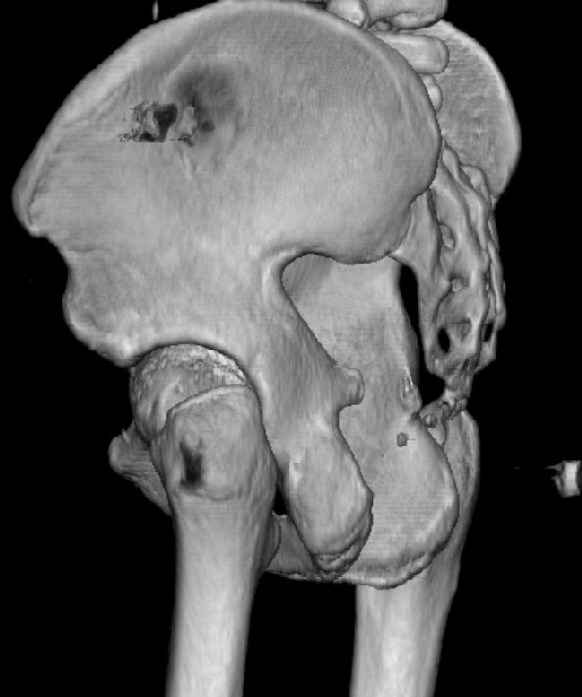

While not claiming to have the best 3D brain around, it appears to me from the limited images available, that the caudal segment is stable from the symphysis to the SI joint on the fracture side. I would love to see the rest of the transverse CT images to see where the fracture line actually exits posteriorly on both the inner and outer tables of the ilium. In my hands,

assuming that the femoral head has followed the cephalad (dome) fragment, I would use an ilioinguinal approach and take down the fracture line from anterior to posterior, distracting with a lamina spreader, if necessary, to clean out and inspect the joint. I would then reduce the cephalad fragment to the caudal fragment using jungbluth or farabeuf clamp and screws and then apply a plate and screws. If the fracture exits posteriorly would you then favor an additional posterior approach to clean out and reduce from that side?

Some more images. Does it help to guess which part of the acetabulum is displaced?

Normal appearing SI joints and a healed posterior column limb... my bet's on caudal segment displacement.